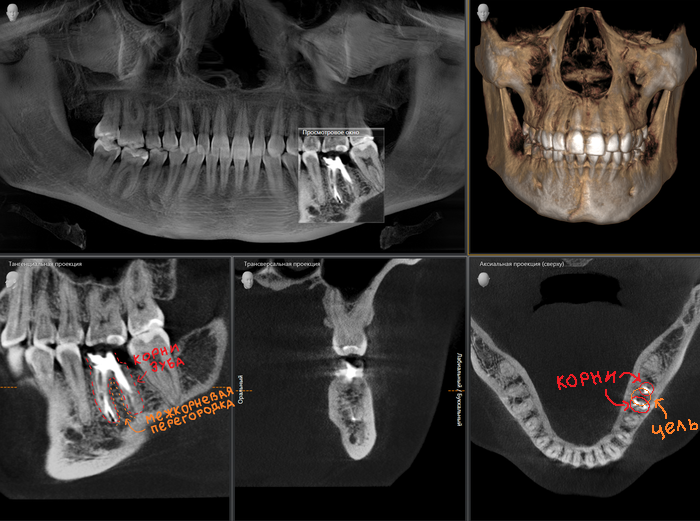

Пример с трехкорневым зубом:

Как мы видим, перегородка в этой области около 3 мм. Данного объема недостаточно для постановки имплантата оптимальной для жевательного зуба длины, следовательно, его нужно увеличивать.

Пример с двухкорневым зубом:

Слева и справа от имплантата на снимке четко видны лунки от только что удаленного зуба. В них набегает кровушка, формируется сгусток, и всё заживает точно так же, как если бы имплантат не устанавливался.

У пациента отсутствуют зубы 6 и 7 на верхней челюсти слева (некоторые фото сделаны при помощи зеркал, поэтому ракурс обзора может меняться):